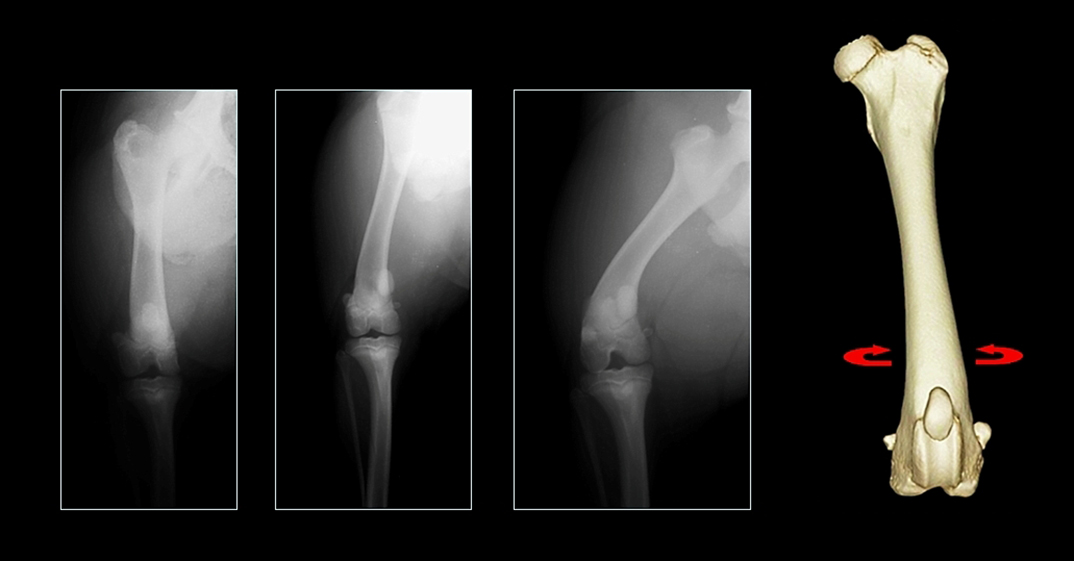

Figure 1 – Craniocaudal projections of the same femur at different amounts of rotation; apparent varus is decreased with internal rotation and increased with external rotation.

Traditional radiographic measurement of femoral varus is sensitive to rotational malpositioning of the femur because of the natural procurvatum of the bone; external rotation (supination) will increase apparent varus, and vice versa (Figure 1). Thus a “true” craniocaudal radiograph must be obtained. Unfortunately the majority of radiographic landmarks to achieve this positioning (including fabellar bisection by the femoral cortices, lesser trochanter position, and nutrient artery foramen position) have been shown to be unreliable. CT permits visualisation of a virtual representation of a femur from any angle, rendering patient positioning irrelevant and facilitating definition of landmarks for rotational and sagittal plane orientation which would be impossible using conventional radiography. Using a volume rendered representation of the femur, superimposition of the medial and lateral condyles, and standardisation of sagittal plane inclination (Figure 2), allows precise quantification of femoral varus.3 Traditional radiographic assessment of femoral torsion is difficult since a long axis projection is usually required. This is straightforward following CT, and a protocol for precise torsion measurement has been described.4